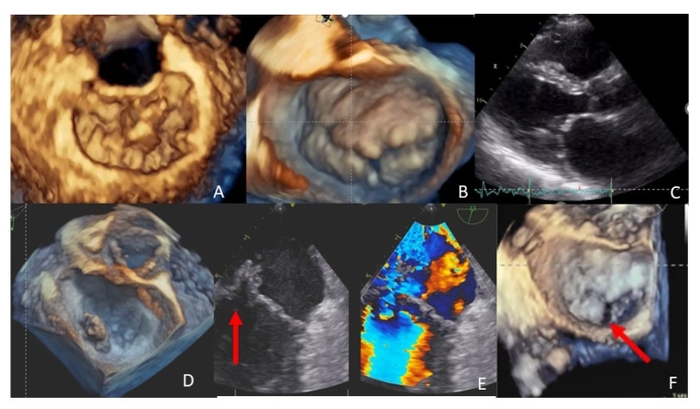

Several transcatheter MV interventions have been proposed for the treatment of MR. At present, edge-to-edge MV repair is used most frequently. This procedure approximates the free edges of the anterior and posterior MV leaflets at the site of the MR jet and emulates surgical edge-to-edge leaflet repair (also called the “Alfieri stitch”), which is differentiated by the concomitant annuloplasty.

A number of echocardiographic evaluations are performed to identify the best candidates, including prolapse/flail location, flail gap, flail width, posterior leaflet length and MV orifice size [10]. After the initial experiences in treating simple A2-P2 related MR, the repair of more complex lesions is now performed more frequently.